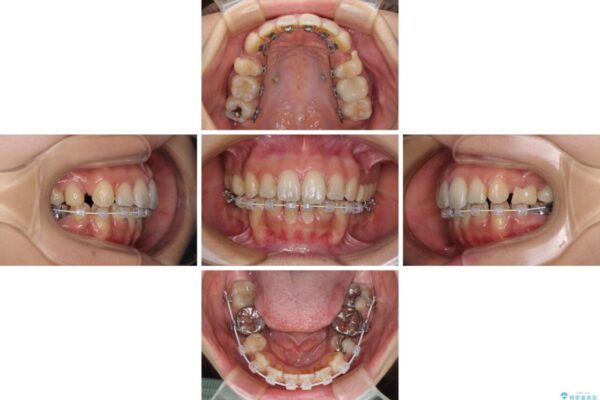

治療途中

• デコボコと口元の突出感 ハーフリンガルでの抜歯矯正 治療途中画像